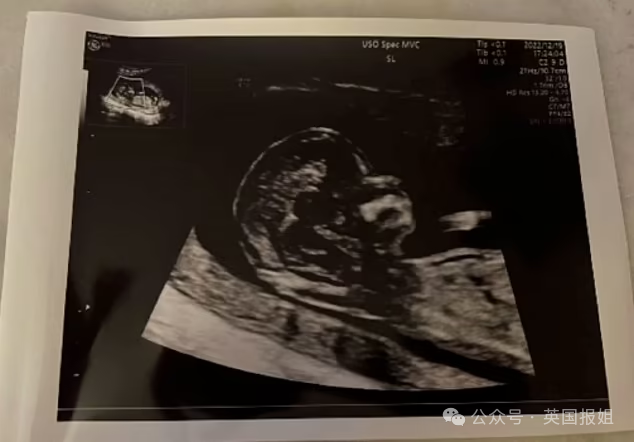

Saga从刚怀孕起,就对成为母亲一事感到兴奋,经常与亲人分享自己怀孕的照片。

日常生活细节中也能看出她满怀期待:精心制作的婴儿床、孩子用的小衣服...她提前做了很多准备,迎接新家庭成员的到来。

“我自己刚当上妈妈,看到这些婴儿的衣服、扫描图、婴儿床,感觉心都要碎了。她真的很想要孩子,谋杀她的畜生不配见到天日。”